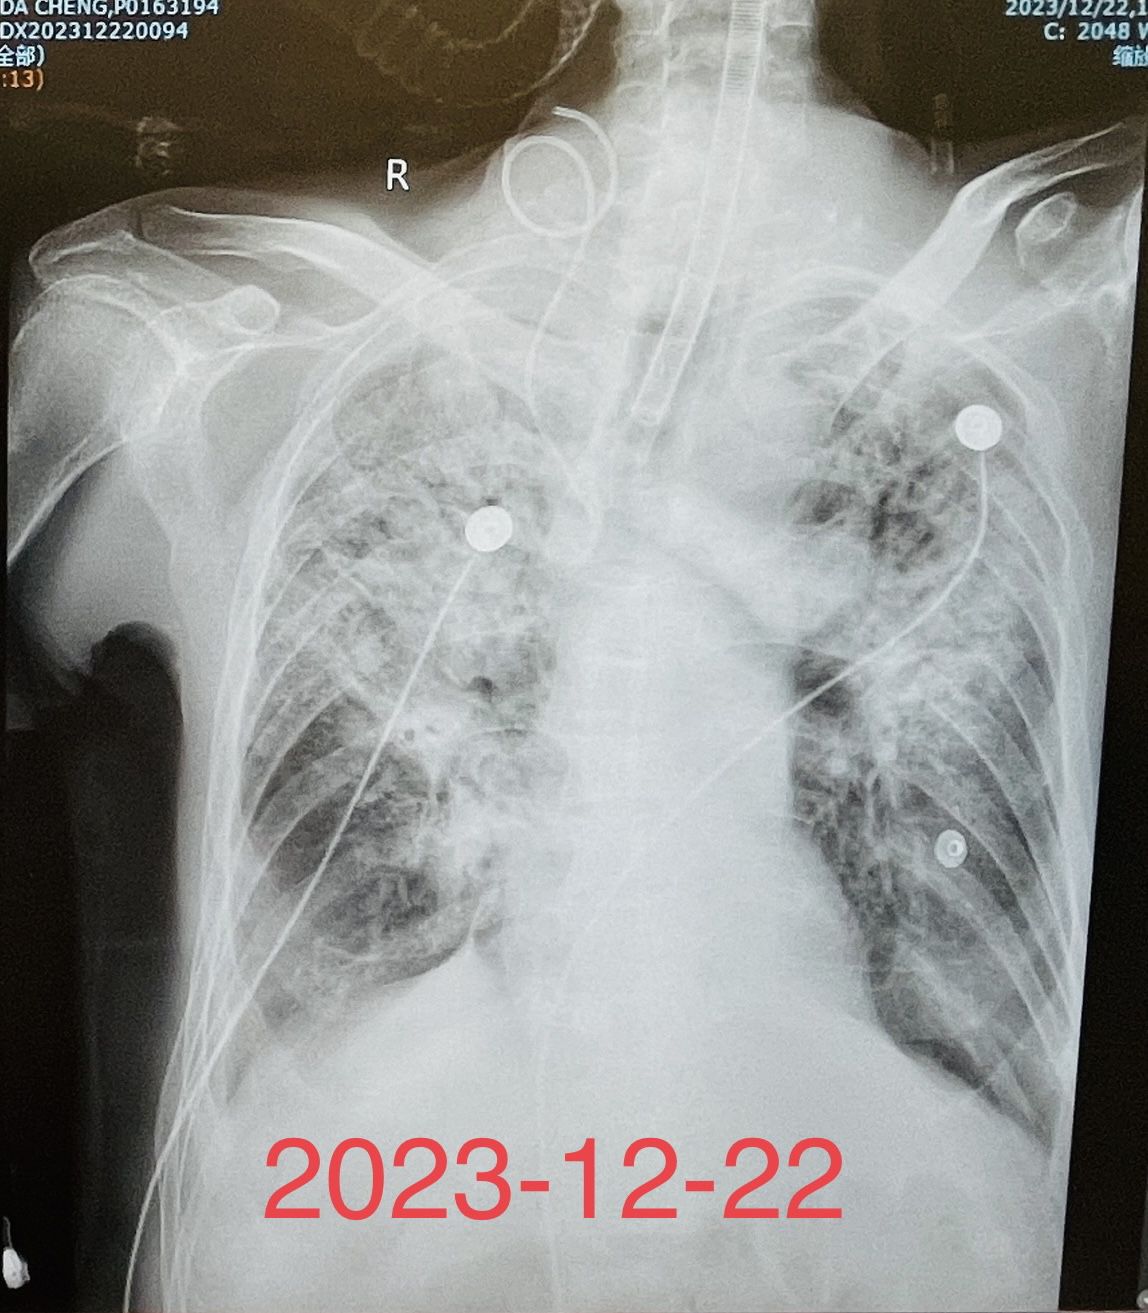

(图1)重症肺炎患者床旁气管镜检查及治疗前后的胸部X线片对比

这是收住呼吸RICU的一个混合感染,重症肺炎合并呼吸衰竭、心力衰竭的患者,经气管插管呼吸机辅助呼吸、床旁气管镜检查明确了病原菌,经积极有效的抗感染治疗,联合提高免疫、营养支持等综合治疗,以及呼吸重症监护室所有医护人员的精心护理,经积极抢救,患者的感染得到了有效控制,病情有了明显的改善。(图1)